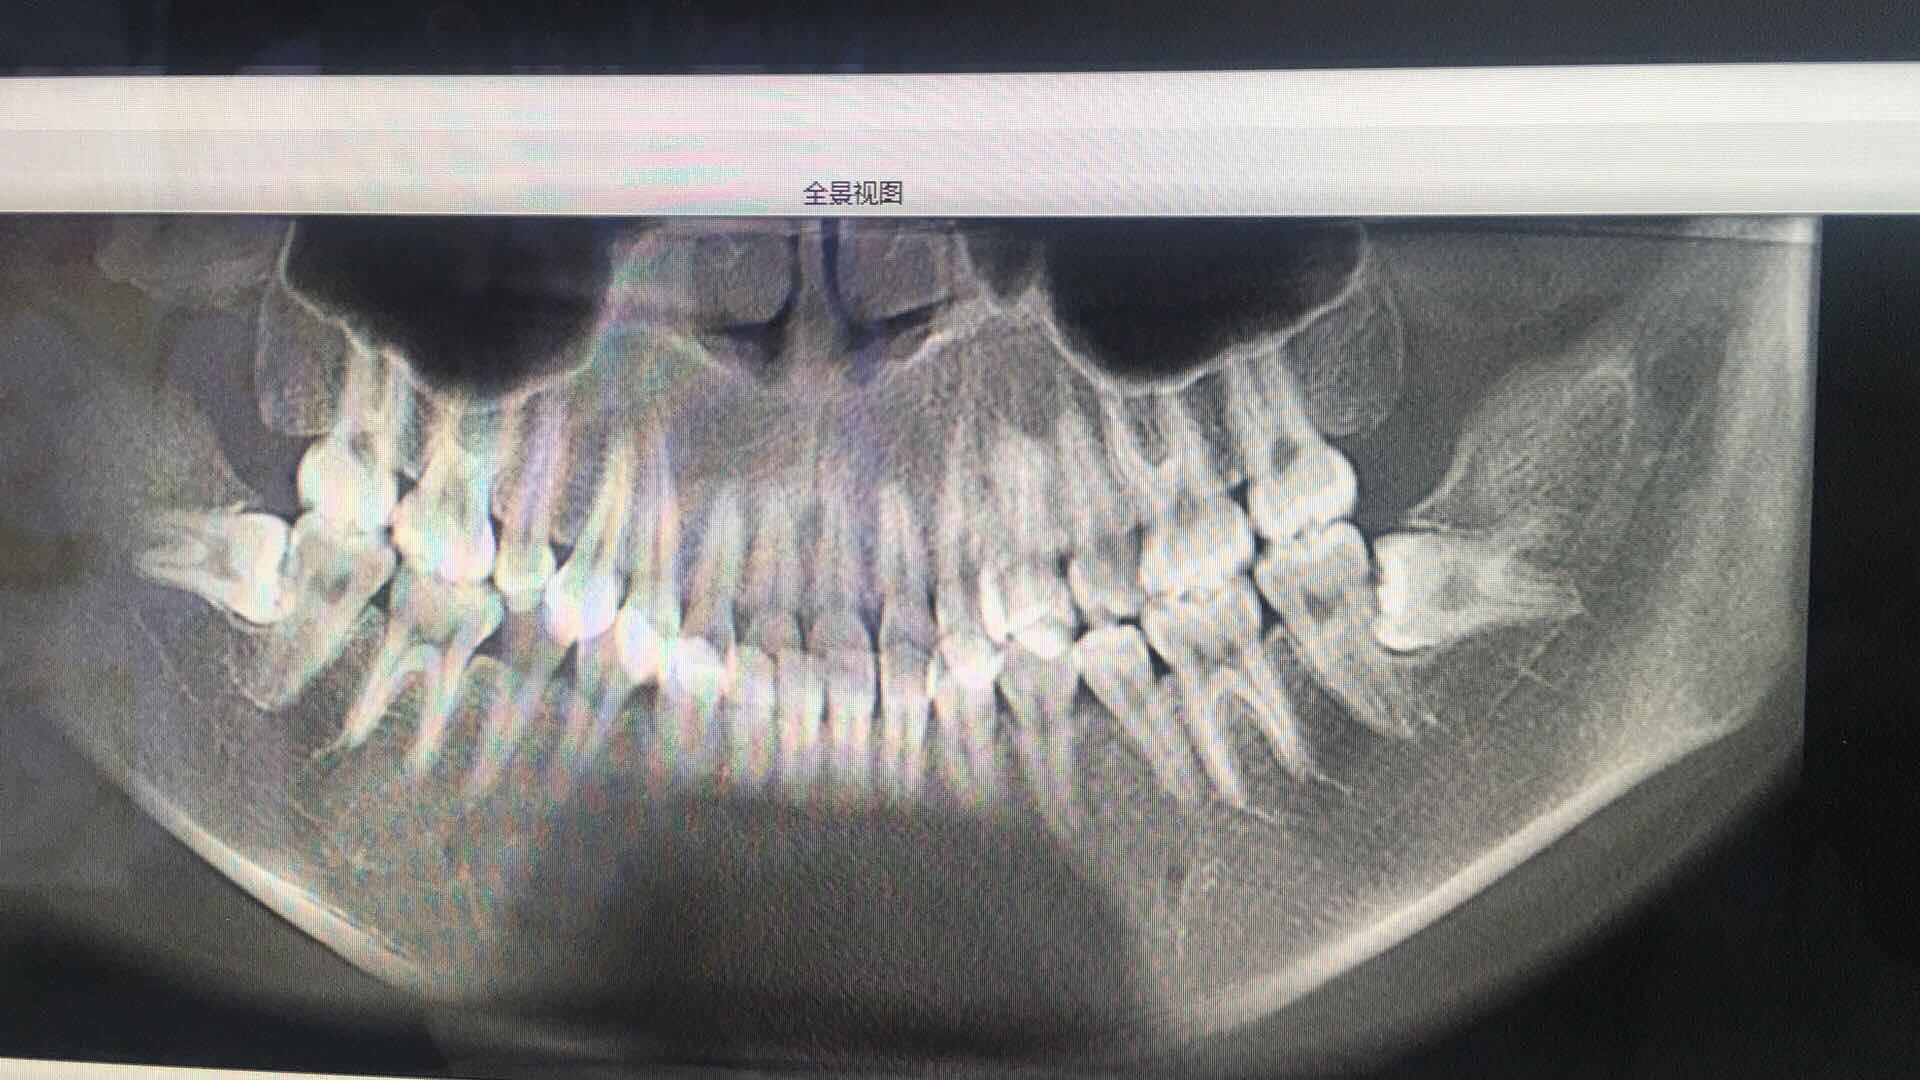

两颗横向阻生智齿,完全埋肉里没露头的骨埋伏

3月28号# 红色圈起来这颗今天下午拔了,削了点骨,缝了几针,十分钟左右。医生技术五星好评,如果不是他非要我留一侧吃饭,我估计两边一起拔了。

4月4号拔另一侧,另一颗有三个牙根,神经从三个牙根正中间穿过。危险系数相当高,祝我好运了。

4月4号拔了左侧智齿(ct上是反过来显示的钱、所以在右边)

这颗智齿危险系数非常大,有三个牙根,神经管从中间几乎是贴着三个牙根穿过(如图二所示),如果伤到神经面部会失去知觉。

图3-5: 是3月28号拔的右侧智齿(从去骨到缝合仅用了几分钟)

图6-7是4月4号的智齿,这个因为危险程度大,时间略长用了十多分种,李明院长医术十分精湛,完全没有伤到神经(忍不住称赞一下)